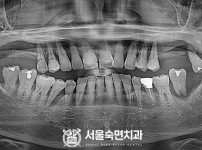

임플란트-전후사진3